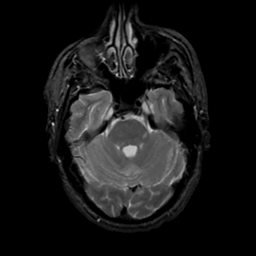

MR Study #13, May 19, 1991 -- Slice #14